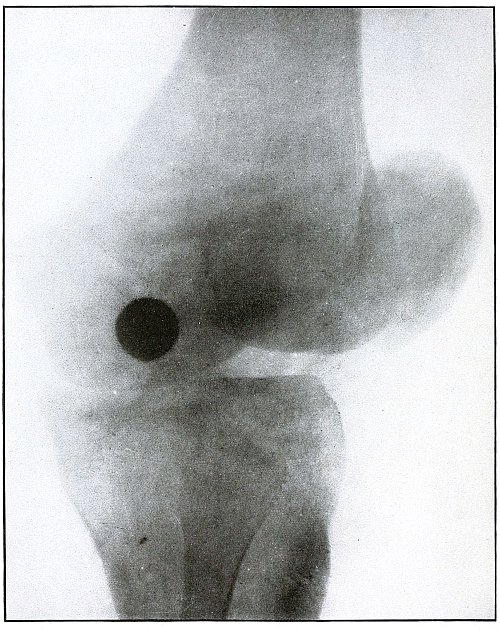

| 128.[Pg 6] |

Gunshot wound, knee |

266 |

| 129. |

Gunshot wound, knee |

268 |

| 130. |

Gunshot wound, knee |

270 |

| 131. |

Gunshot wound, knee |

272 |

| 132. |

Gunshot wound, knee |

274 |

| 133. |

Gunshot wound, knee |

276 |

| 134. |

Gunshot wound, knee |

278 |